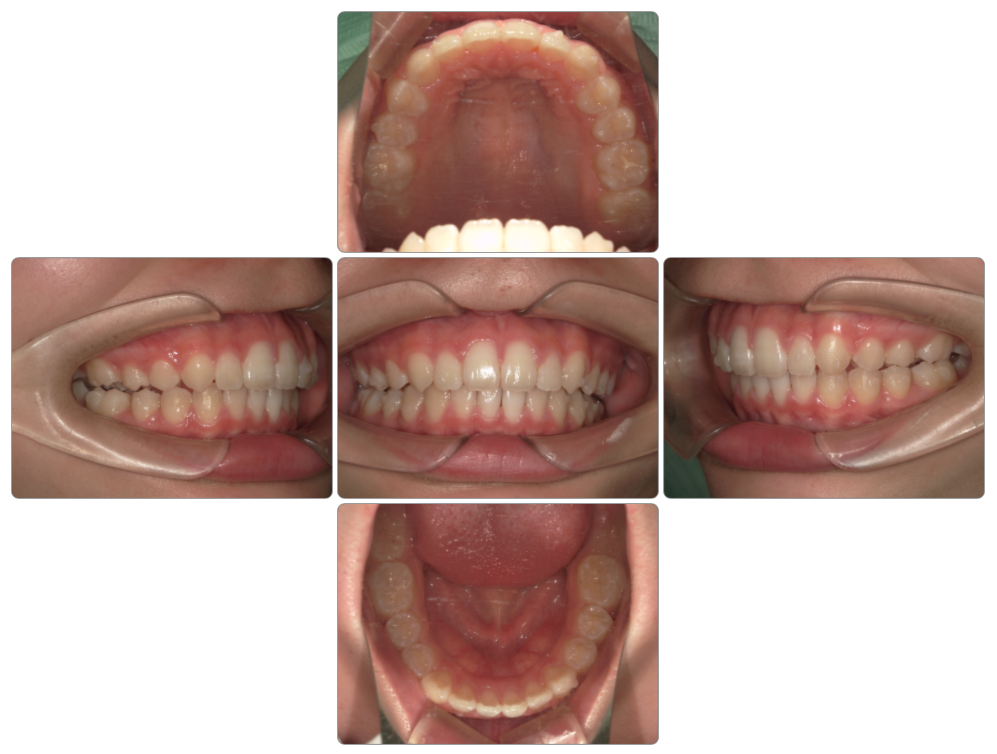

上顎前突の治療例

Before

after

| 初診時 | 8歳1か月 |

| 治療期間 | 2年2ヵ月 |

| 費用 | ¥550,000 調整料・¥5,500/月 |

| 使用装置 | マイオブレイス・BWS |

| リスクと副作用 | |

| 原因と考察 | 頚椎成長が足りないために下顎骨の高さが育っていません。このことが口腔の高さが不足しています。マイオブレイスを使用していると厚みがある分下顎骨の高さがますのでこのように過蓋咬合が改善に導かれます。ただ全身の問題で考えると頚椎成長を促すような生活指導は原因除去という点では欠かせません。 |